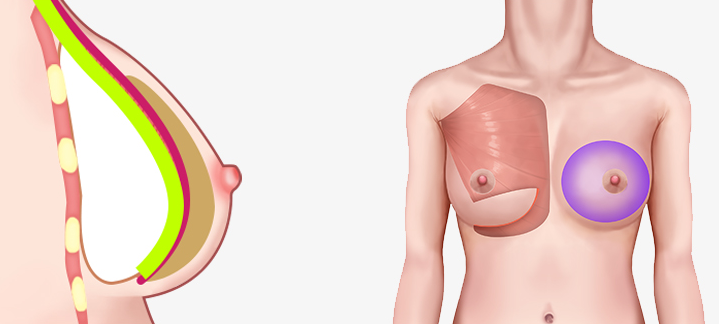

โดยเสริมซิลิโคนใต้กล้ามเนื้อ และเหนือกล้ามเนื้อ อัตราการเกิดการสร้างทรงกลมต่ำกว่าการเสริมแบบมีสายมาก

สามารถสร้างสัมผัสตามธรรมชาติและเส้นใต้เต้านมได้ การเปลี่ยนแปลงรูปร่างมีน้อย

โดยเสริมซิลิโคนใต้กล้ามเนื้อ และเหนือกล้ามเนื้อ อัตราการเกิดการสร้างทรงกลมต่ำกว่าการเสริมแบบมีสายมาก

สามารถสร้างสัมผัสตามธรรมชาติและเส้นใต้เต้านมได้ การเปลี่ยนแปลงรูปร่างมีน้อย

มักจะใช้กล้ามเนื้อปิดเนื้อเยื่อบางๆของผิวหนัง เพื่อให้เห็นซิลิโคน และความกังวลน้อยลง

เนื่องจากความกดดันของกล้ามเนื้อ จึงมีความเสี่ยงน้อยที่ตำแหน่งของซิลิโคนจะเคลื่อนที่ได้ และความน่าจะเป็นที่จะเกิดคลื่นริ้วรอยก็มีน้อยด้วย

บริเวณที่มีกล้ามเนื้อจะมีผิวหนังและเนื้อเยื่ออ่อนที่ยืดไม่ค่อยออก แต่บริเวณที่ไม่มีกล้ามเนื้อปกคลุมนั้นค่อนข้างที่จะ

ผิวหนังและเนื้อเยื่อที่เชื่อมต่อกันจะยืดได้ดีและช่วยให้เส้นโค้งธรรมชาติยังคงอยู่แม้ในกรณีที่ด้านล่างของหน้าอกแน่นมาก